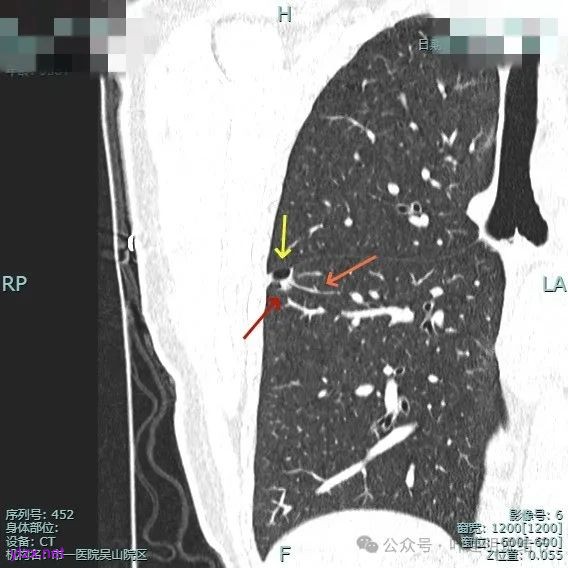

非薄层平扫上这个层面比较明显,似一囊腔,壁厚薄欠均匀。

薄层上看病灶贴着叶间裂与胸膜,此层囊壁薄,囊腔明显。

囊壁局部有增厚。

囊壁局部较厚,但囊壁内也是有小空泡的,病灶贴着胸膜。

病灶部分囊壁是混合磨玻璃成分的,整体轮廓较清。

边缘区也有偏实性成分,磨玻璃成分也还是明显的,有微小血管进入。

靶重建的影像上看,病灶的囊壁明显厚薄不均,有小血管进入,一侧的边似就是斜裂的样子。

囊壁有磨玻璃成分,边缘毛糙,有少许偏实性成分,仍有磨玻璃成分。

血管走向病灶,囊壁略不均。

此层见囊壁有较明显实性成分,血管进入明显。叶间裂侧平直。

混合密度,收缩力不明显,血管进入明显。

囊壁混合密度,整体轮廓清。

表面不平,血管进入,囊壁厚薄不均,紧贴叶间裂。

囊壁里面也有小空泡征。

混合密度但还是太致密,内壁毛糙不平。

病灶轮廓清楚,囊壁厚薄不均,贴着叶间裂与胸膜。